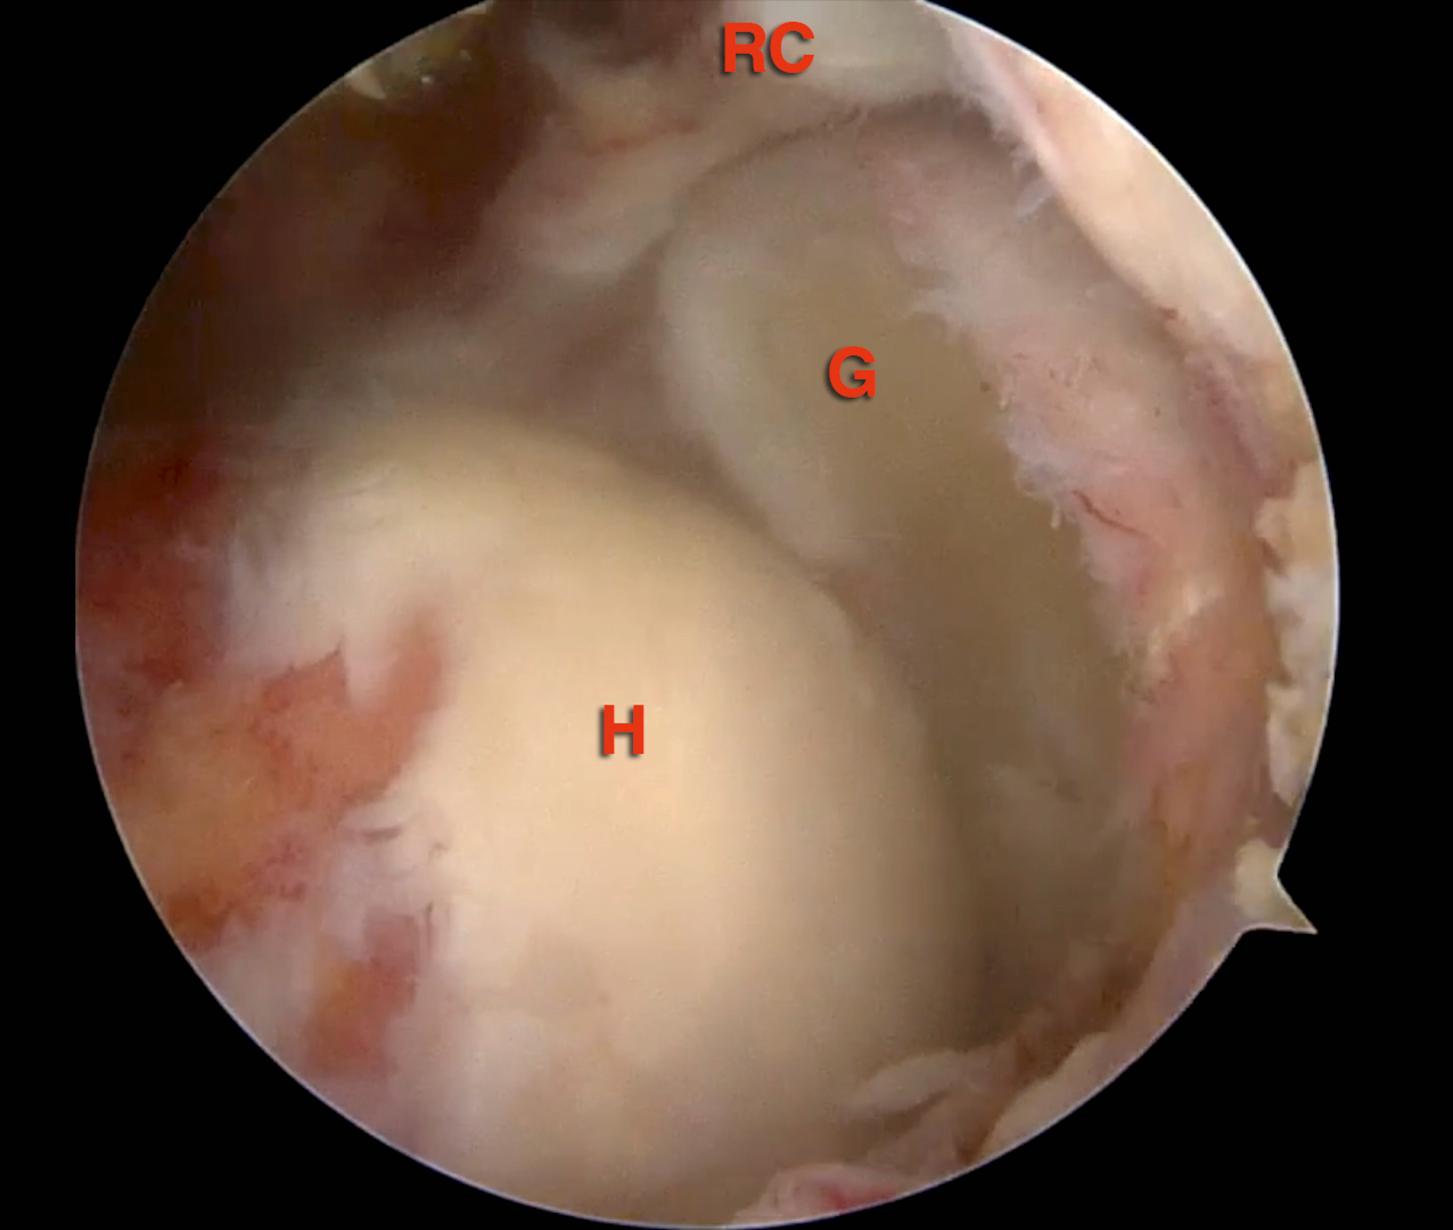

FIG. 7.3, Intraoperative arthroscopic view of the irreparable cuff tear in the right shoulder. Scope is positioned in an anterosuperolateral portal. G , glenoid; H , humeral head; RC , rotators cuff remnant.